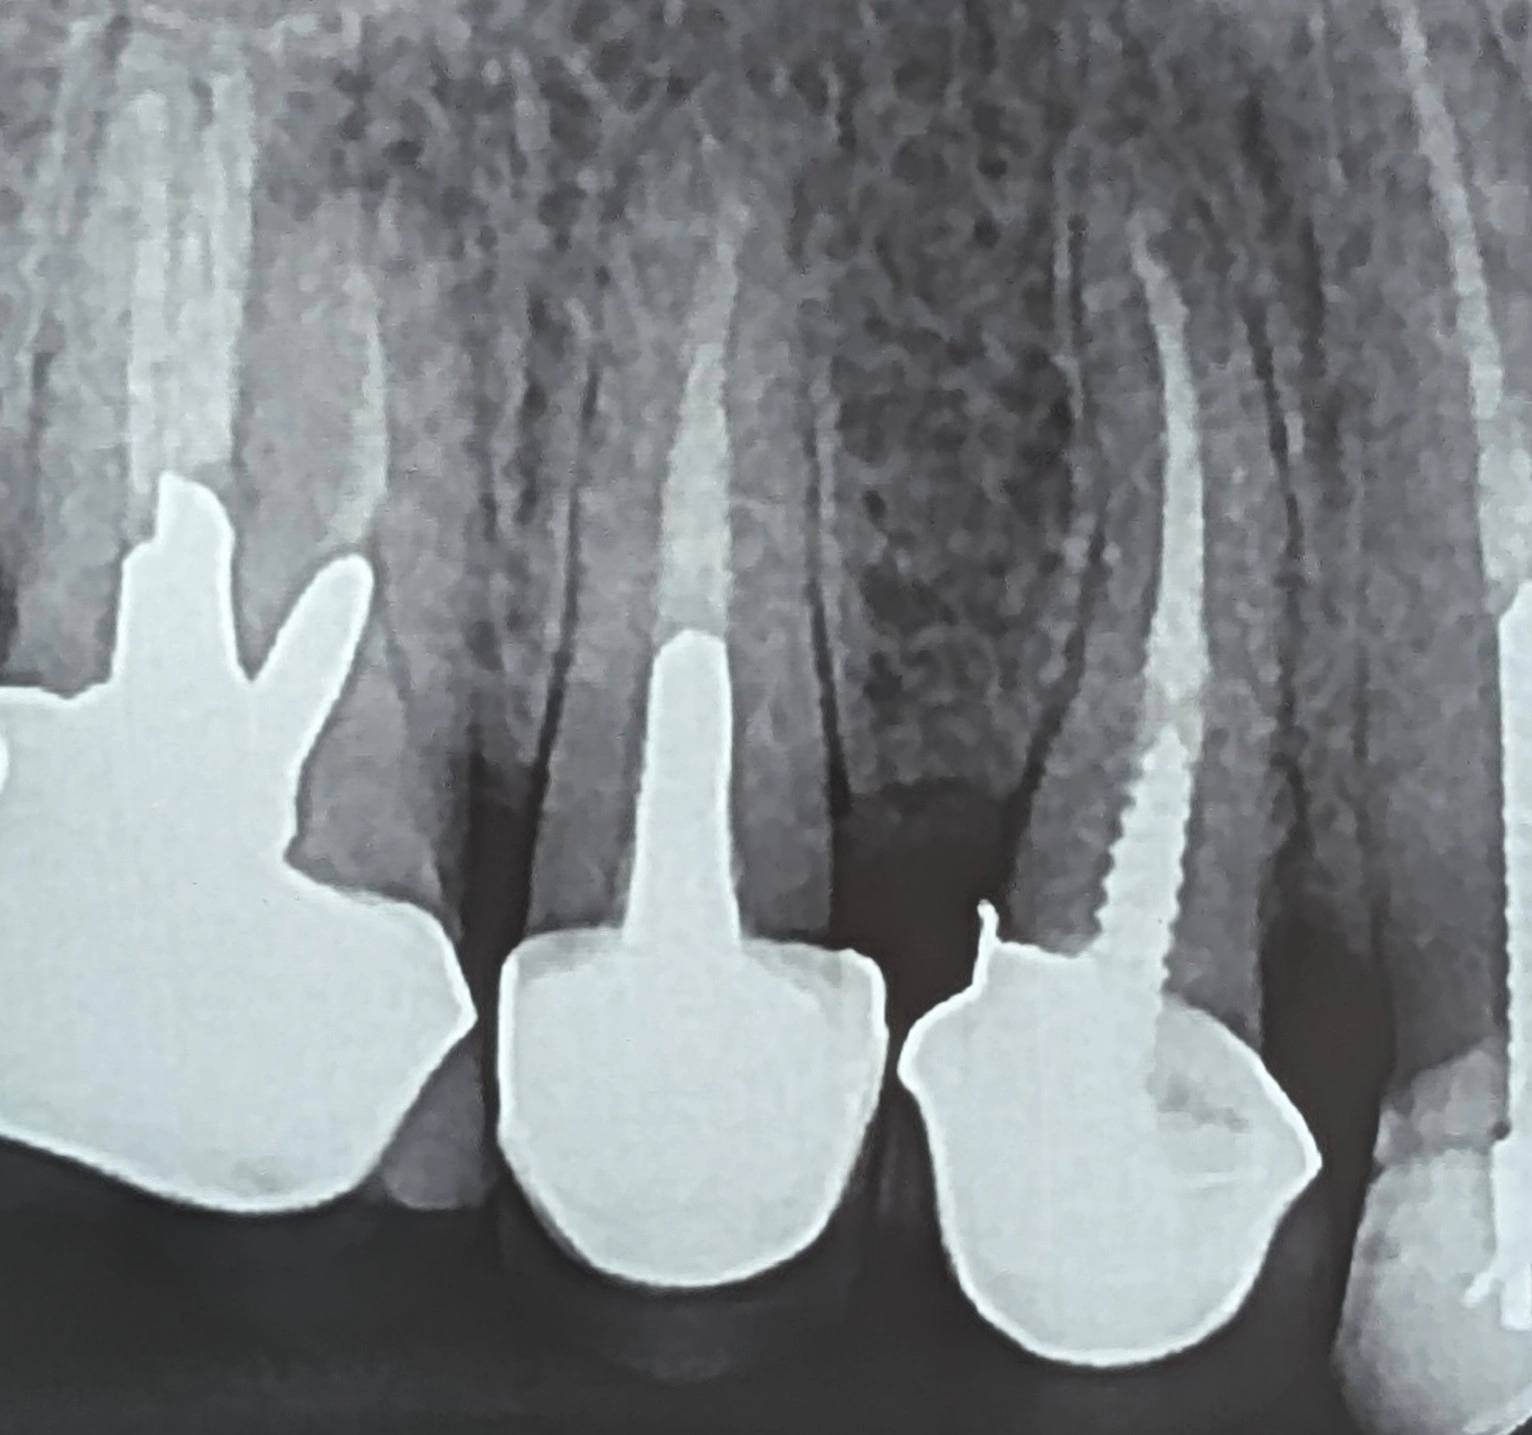

در ارزیابی اولیه، محدودیتهای پانورامیک در تشخیص جزئیات ساختاری مدنظر قرار گرفت

و رادیوگرافی پریاپیکال از ناحیه تهیه شد.

در PA،

نشانهای از پوسیدگی ثانویه گسترده، ضایعه اپیکالی یا تخریب غیرمعمول ساختار ریشه مشاهده نشد.